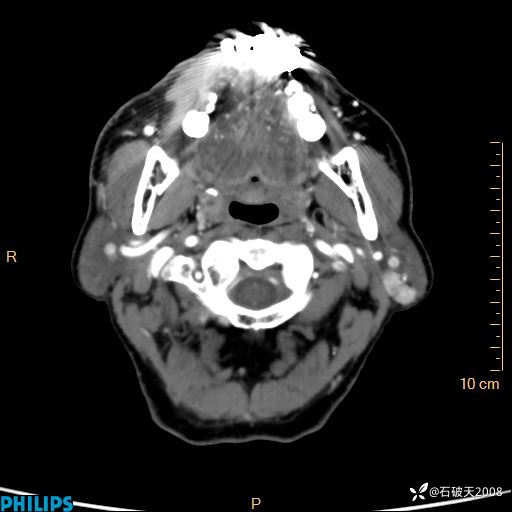

动脉期